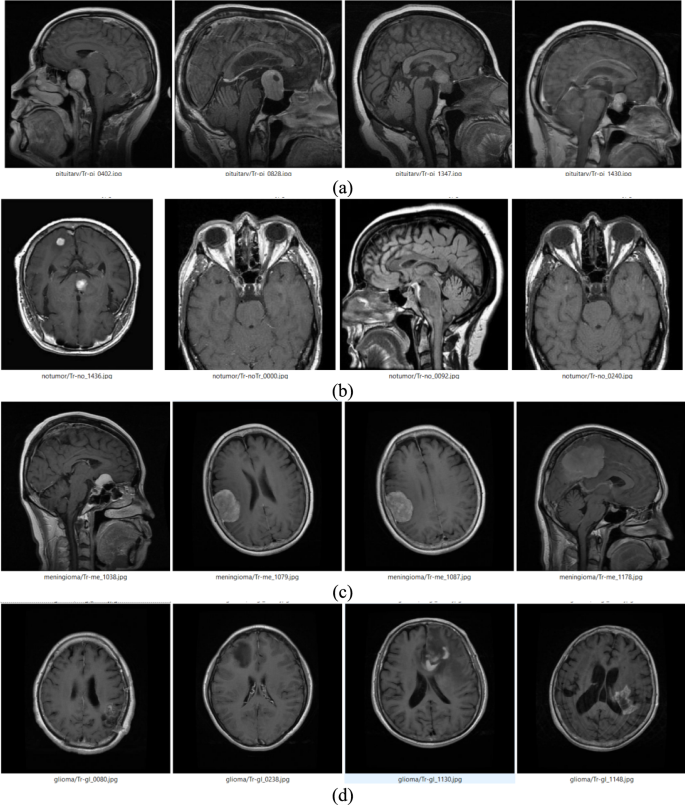

Figure 2 shows MRI images from a dataset showcasing four BT categories: pituitary, no-tumour, meningioma, and glioma. Pituitary tumours are located near the basis of the brain and often appear as well-defined lesions in the Sella region. No-tumor images show intact brain structures without abnormal growths. Meningioma tumours appear as distinct growths arising from the meninges and often have clear boundaries. Glioma tumours originate in glial cells and frequently appear as irregular, infiltrative masses within brain tissue. The Fig. 2 represents the visual distinctions between tumour types and normal brain scans, aiding in understanding the dataset’s composition and the challenges in automated detection systems.

Sample images of different brain tumour (a) Pituitary (b) No-Tumor (c) Meningioma (d) Glioma.